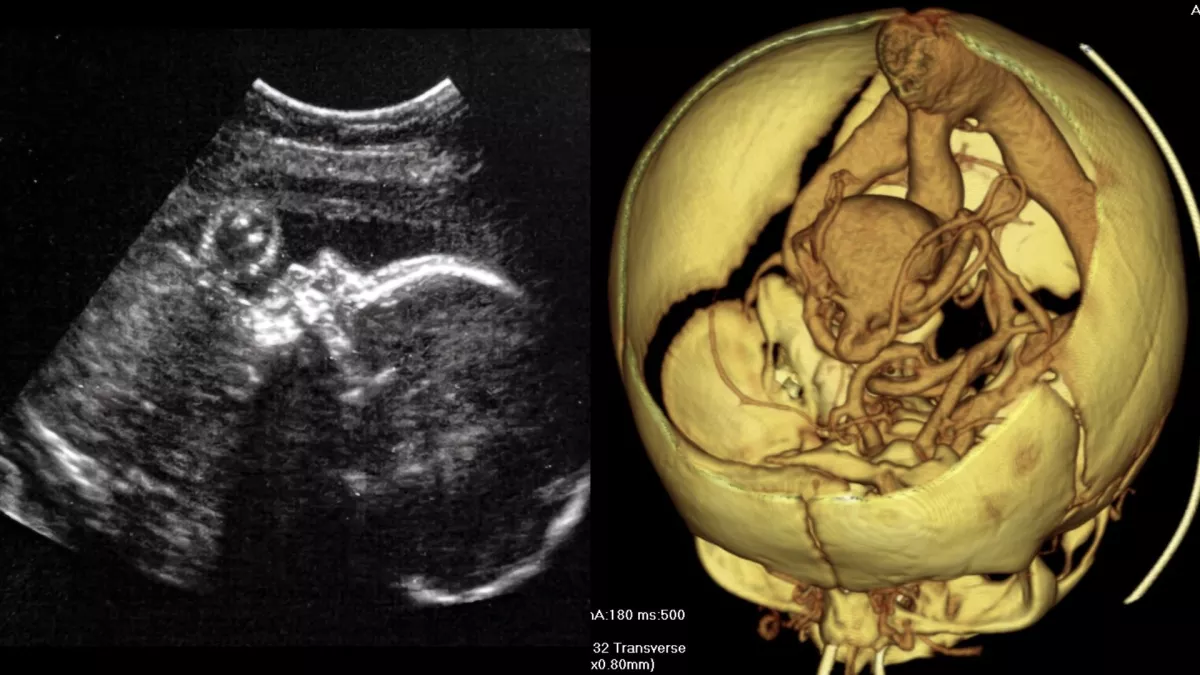

| Hình ảnh bên trái cho thấy kết quả siêu âm của một em bé khỏe mạnh trong tử cung. Hình ảnh bên phải cho thấy sơ đồ 3D của các mạch máu trong não của trẻ sơ sinh, cho thấy một dị tật được gọi là "dị dạng tĩnh mạch Galen" |

Ở những thai nhi mắc dị tật hiếm gặp gọi là "VOGM", một số động mạch trong não kết nối trực tiếp với tĩnh mạch chính, thay vì kết nối đúng cách với các mao mạch.

Trong VOGM, một số động mạch nhất định trong não không liên kết với các mao mạch — các mạch máu phân nhánh, mỏng manh giúp làm chậm lưu lượng máu — như bình thường. Thay vào đó, các động mạch đổ máu vào các tĩnh mạch ở đáy não và máu chảy với áp suất cao. Lưu lượng máu với áp suất cao có thể gây suy tim sung huyết, huyết áp cao trong động mạch phổi (tăng huyết áp phổi), tổn thương và mất mô não hoặc đầu to (não úng thủy).